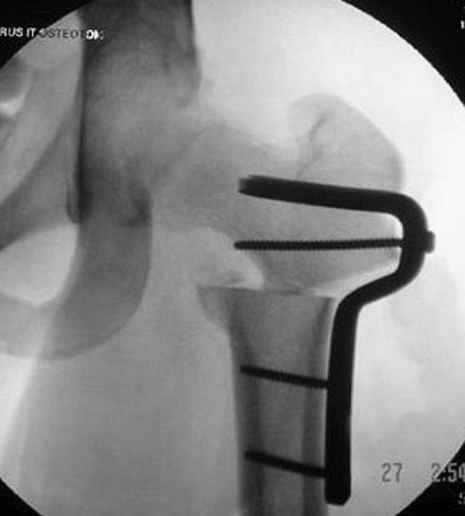

Несколько снимков из моей коллекции, чтобы разьяснить, почему мы до сих пор делаем различные варианты остеотомии.

На рисунке N1 предоперационный план лечения ложного сустава шейки бедра- линия ложного сустава, угол и направление введения импланта, клиновидная остеотомия в градусах и миллиметрах, второй снимок после коррекции, расчет, на сколько удлиняется конечность и размеры импланта;

N3 рисунок окончательный снимок, после операции моя рентгенограмма должен выглядеть примерно как эта картина. На N4 снимке клин перед удалением; N5 послеоперации 3 нед.; N6 окончательная рентгенограмма.

(доложен в Ст. Петербурге 2003 и в Москве 2004)

варус при проксимальном отделе 95 градусной пластиной.